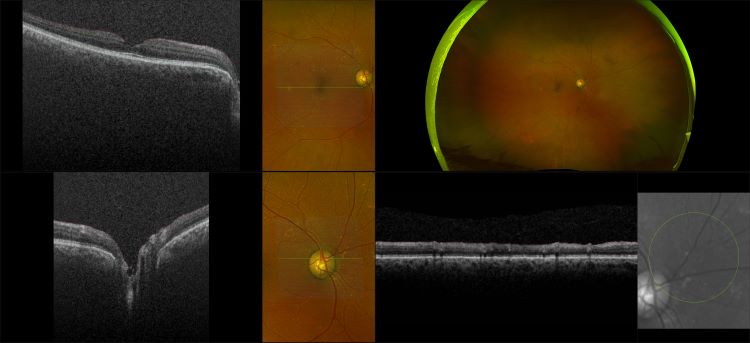

Monaco - Pigment Epithelial Detachment, RG, OCT